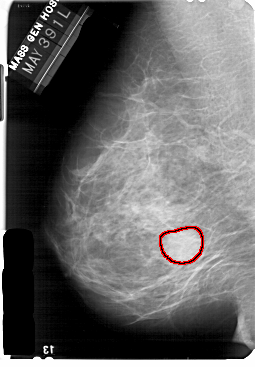

A_1733_1.LEFT_MLO

LEFT_MLO LINES 5491 PIXELS_PER_LINE 3811 BITS_PER_PIXEL 12 RESOLUTION 43.5 OVERLAY

FILE: A_1733_1.LEFT_MLO.OVERLAY

TOTAL_ABNORMALITIES 1

ABNORMALITY 1

LESION_TYPE MASS SHAPE LOBULATED MARGINS CIRCUMSCRIBED

ASSESSMENT 3

SUBTLETY 5

PATHOLOGY BENIGN

TOTAL_OUTLINES 1

BOUNDARY